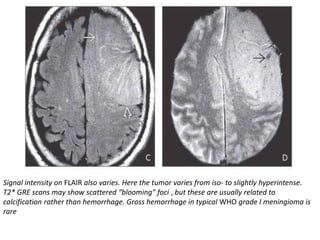

Signal intensity on FLAIR also varies. Here the tumor varies from iso- to slightly hyperintense.

T2* GRE scans may show scattered “blooming” foci , but these are usually related to

calcification rather than hemorrhage. Gross hemorrhage in typical WHO grade I meningioma is

rare

Large convexity meningioma.The tumor has flat base toward the dural surface, “buckles” the cortex and GM-WM interface inward. Meningiomas are most commonly iso- to slightly hypointense with cortex on T1WI. T2 signal intensity varies. Here the tumor is iso-/slightly hyperintense relative to cortex. “Sunburst” of dural vessels is well seen. Note CSF-vascular “cleft,” clearly seen here , as is the displaced GM-WM interface

Signal intensity onFLAIR also varies. Here the tumor varies from iso- to slightly hyperintense. T2* GRE scans may show scattered “blooming” foci , but these are usually related to calcification rather than hemorrhage. Gross hemorrhage in typical WHO grade I meningioma is rare